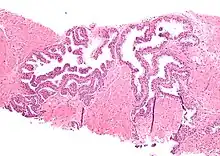

Micrograph showing high-grade prostatic intraepithelial neoplasia. H&E stain.

High-grade prostatic intraepithelial neoplasia (HGPIN) is an abnormality of prostatic glands and believed to precede the development of prostate adenocarcinoma (the most common form of prostate cancer).[1][2]

It may be referred to simply as prostatic intraepithelial neoplasia (PIN). It is considered to be a pre-malignancy, or carcinoma in situ, of the prostatic glands.

HGPIN typically has one of four different histologic patterns:[2]

Microscopically, PIN is a collection of irregular, atypical epithelial cells. The architecture of the glands and ducts remains normal. The epithelial cells proliferate and crowding results in a pseudo-multilayer appearance. They remain fully contained within a prostate acinus (the berry-shaped termination of a gland, where the secretion is produced) or duct. The latter can be demonstrated with special staining techniques (immunohistochemistry for cytokeratins) to identify the basal cells forming the supporting layer of the acinus. In prostate cancer, the abnormal cells spread beyond the boundaries of the acinus and form clusters without basal cells. In HGPIN, the basal cell layer is disrupted but present. PIN is primarily found in the peripheral zone of the prostate (75-80%), rarely in the transition zone (10-15%) and very rarely in the central zone (5%), a distribution that parallels the zonal distribution for prostate carcinoma.[7]

Several architectural variants of PIN have been described, and many cases have multiple patterns. The main ones are tufting, micropapillary, cribriform, and flat. Although these different appearances may cause confusion with other conditions, they have not been found to be of clinical importance. Rarer types are signet-ring-cell, small-cell-neuroendocrine, mucinous, foamy, inverted, and with squamous differentiation.[3]